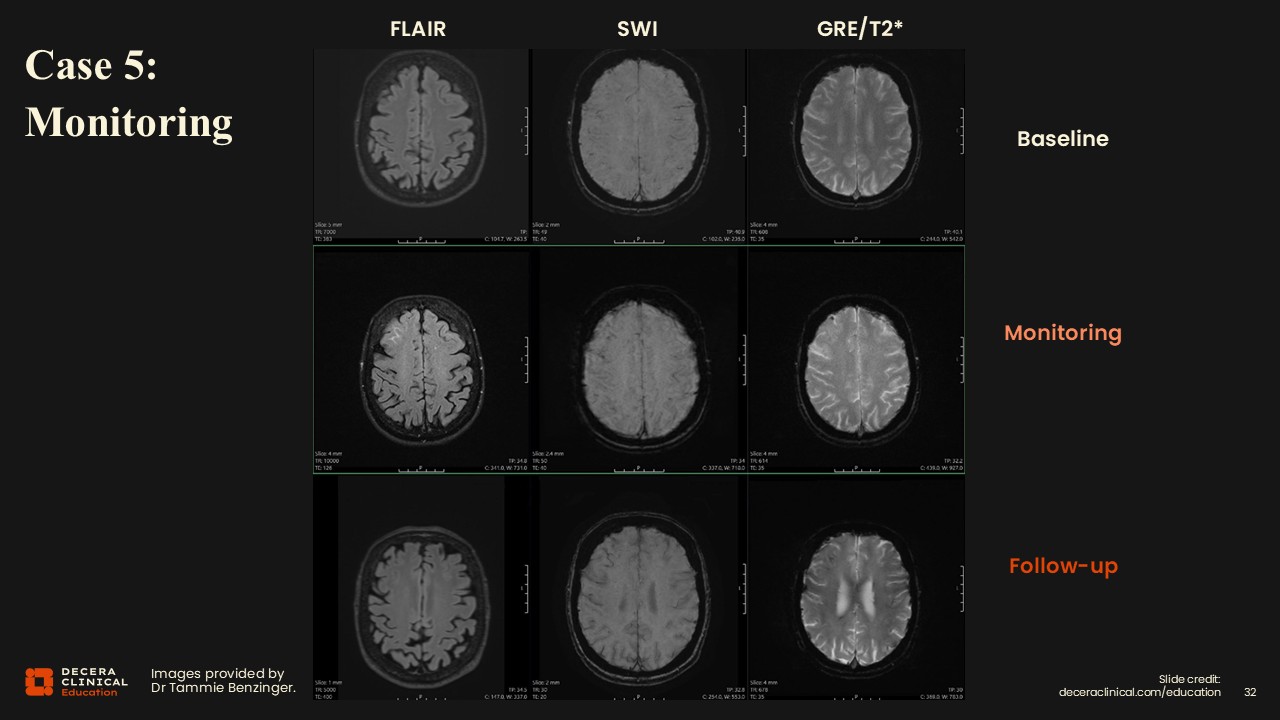

Case 5: ARIA Monitoring in Comparison with CT Scan

Dr Benzinger:

In this case, vasogenic edema in the right frontal lobe becomes more visible in the enlarged image.

Case 5: ARIA Monitoring and CT Scan

The trick is that there is also a little bit of signal loss on SWI, and comparison with baseline confirms that these are not just veins in that area, but this represents new change.

Case 5: ARIA Monitoring (Grading)

For classification, this is consistent with mild ARIA-E along with new susceptibility signal loss indicating additional microhemorrhages, graded as moderate ARIA-H based on lesion count. The plan would be to place a phone call to the clinical treatment team, correlate for symptoms, and recommend a follow-up scan.

Case 5: ARIA Not Seen on Head CT and CTA

This is another example where a corresponding head CT failed to show the edema or hemorrhagic changes clearly. It is not well visualized, although you might think that it would be. This underscores that CT is not sensitive for typical ARIA findings and that MRI is preferred for detection and follow-up.